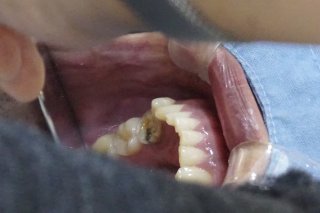

나이가 들면서 치아가 약해지면 음식을 제대로 씹지 못하거나 발음이 부정확해져 불편을 겪는 경우가 많습니다. 그러나 임플란트 시술은 비용이 높아 쉽게 결정하지 못했던 것이 사실입니다. 많은 어르신들이 경제적 부담 때문에 필요한 치료를 미루고 있으며, 그로 인해 영양 불균형이나 자신감 상실로 이어지기도 합니다.

1. 자연 치아와 유사한 저작 기능으로 음식 섭취가 편리함

4. 주변 치아를 손상시키지 않고 독립적으로 식립 가능